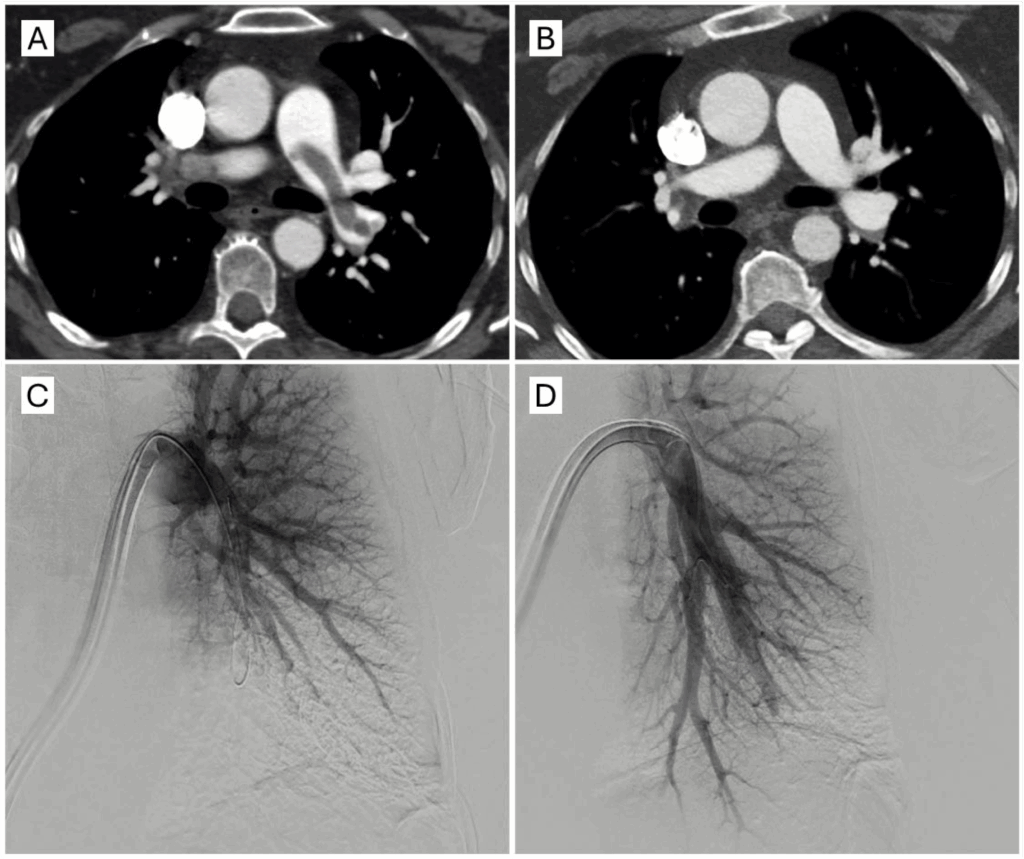

(A) Pre-procedure CT and (B) 48 hours post-procedure CT (C) Left pre-aspiration angiogram (D) Left post-aspiration angiogram. Case images provided by Dr. Samuel Horr (TriStar Centennial Medical Center, Nashville, TN).